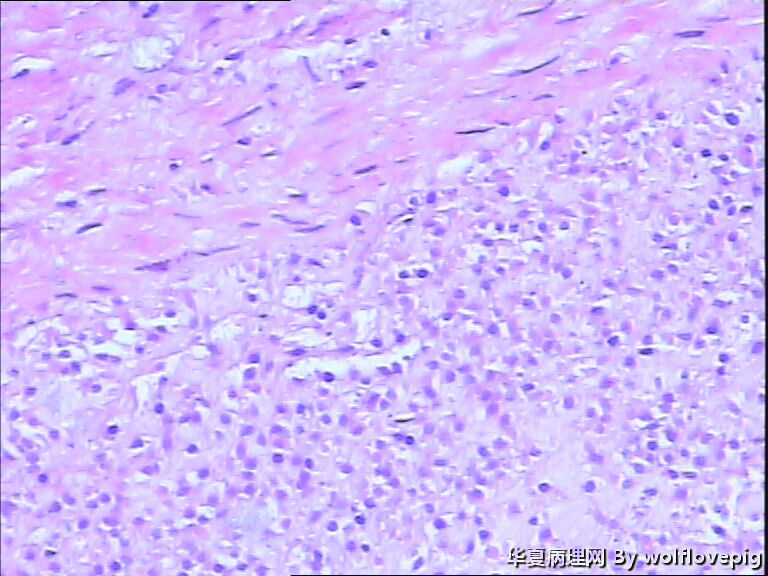

求助!肌瘤变性?

图1